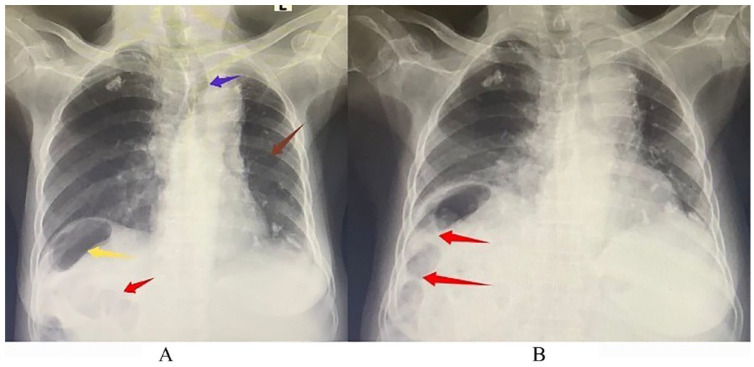

奇莱迪蒂征是一种罕见的放射学发现,其特点是结肠位于肝脏和右半膈之间。它是假性腹腔积气的原因之一,常常被误认为是真性腹腔积气。在本文中,我们介绍了一例 73 岁女性病例,她既往有肺结核病史,因进行性腹胀伴有早饱、双足浮肿、全身乏力、乏力加重和体重减轻到我院就诊。经过评估,她被诊断为肝硬化和慢性淋巴细胞白血病。她的胸片还意外显示右半膈下有空气,并伴有符合奇莱迪蒂征的胸膜皱褶。由于她没有腹膜炎的征象,最终她接受了肝硬化和慢性淋巴细胞白血病的治疗,没有进行任何手术干预。本病例报告旨在提高临床医生对这种罕见放射学征象的认识,以防止误诊导致不必要的外科手术。

Chilaiditi's sign is a rare radiological finding characterized by colonic interposition between the liver and the right hemidiaphragm. It is a cause of pseudopneumoperitoneum which is often mistaken for true pneumoperitoneum. In this article, we present the case of a 73-year-old female with a previous history of pulmonary tuberculosis, who reported to our hospital with progressive abdominal distension associated with early satiety, bipedal swelling, generalized weakness, worsening fatigue, and weight loss. Following evaluation, she was diagnosed with liver cirrhosis and chronic lymphocytic leukemia. Her chest radiograph also incidentally showed air under the right hemidiaphragm with haustral folds consistent with Chilaiditi's sign. Since she did not have signs of peritonitis, she was eventually treated for liver cirrhosis and chronic lymphocytic leukemia without undergoing any surgical intervention. This case report seeks to create awareness among clinicians about this rare radiological sign in order to prevent misdiagnosis leading to unnecessary surgical procedures.